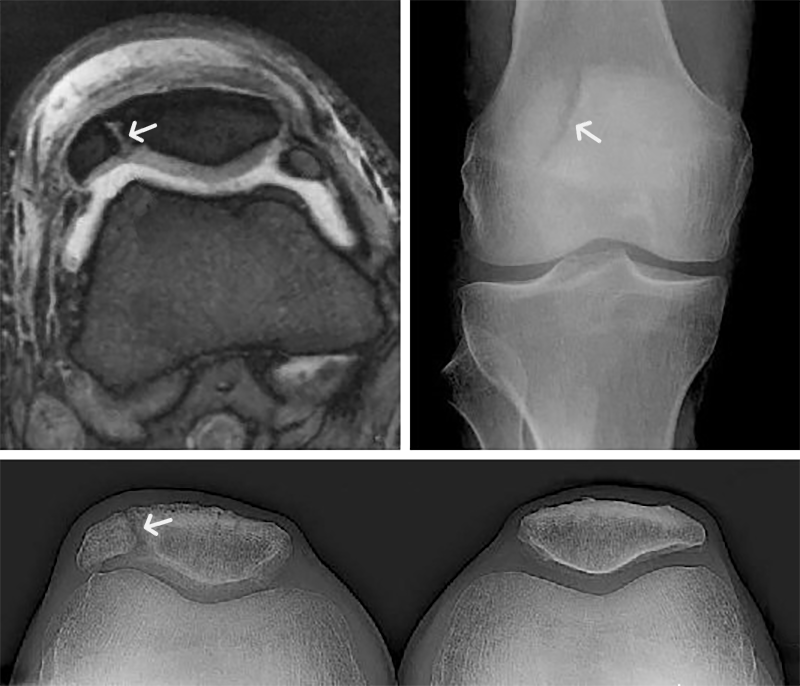

Patella bipartita

Gelegentlich findet man im Röntgen oder Kernspin (oben links) schlimme Brüche [Frakturen] der Kniescheibe, die gar keine sind. Es handelt sich um eine harmlose Verknöcherungsstörung, die zweigeteilte Kniescheibe [patella bipartita]. Das abgelöste Teilstück [Fragment] liegt meist oben außen.